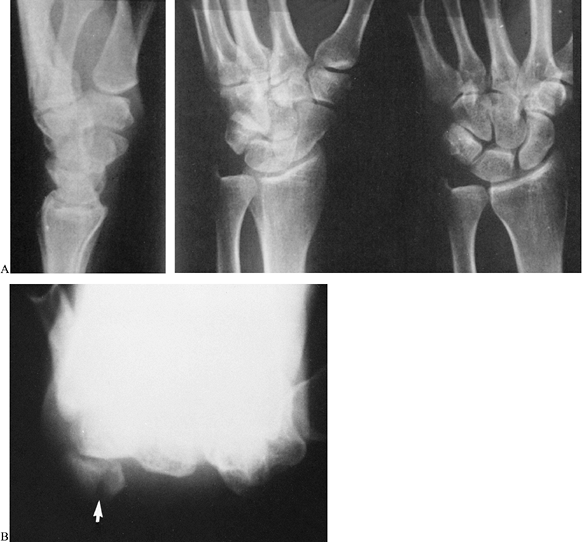

fourth and fifth metacarpals (Fig. 42.17).

![]() |

|

Figure 42.17. A,B: Oblique and lateral radiographs show a coronal fracture through the dorsal aspect of the hamate (arrows) associated with dorsal subluxations of the bases of the fourth and fifth metacarpals.